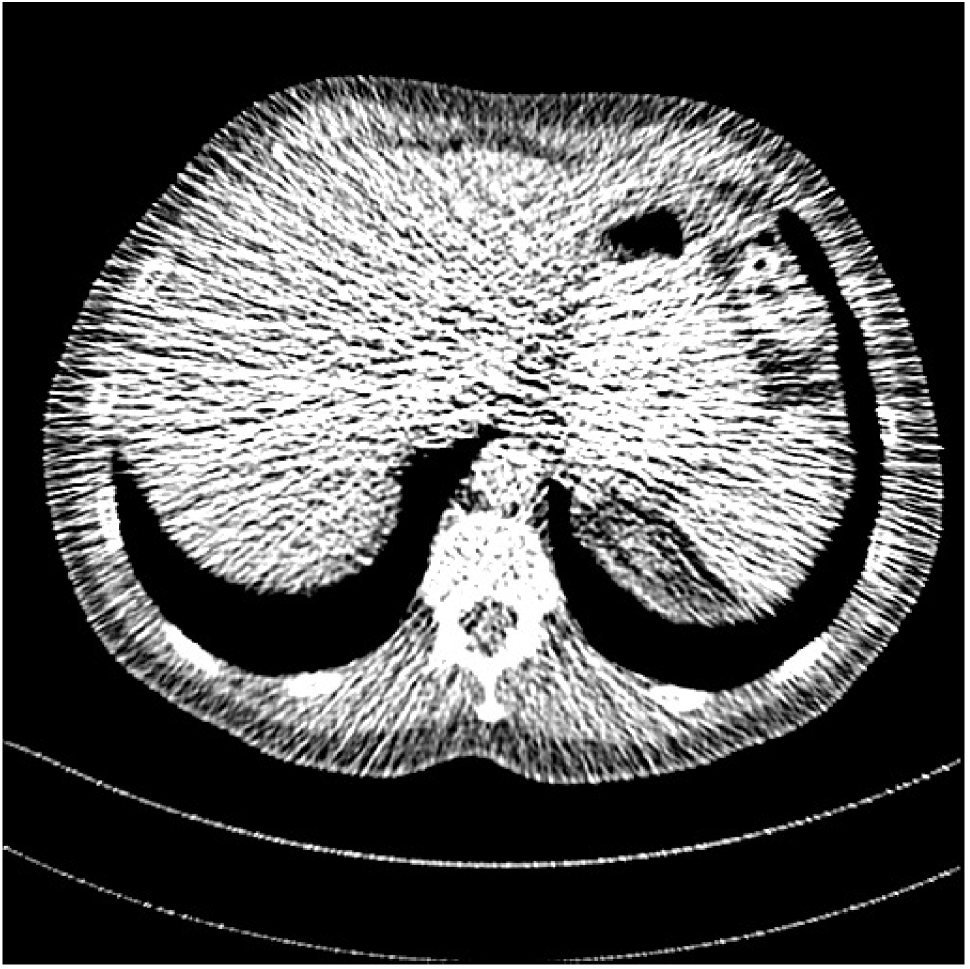

Fig. 3: Three examples (from top to bottom) of the reconstructed testing images using Momentum-Net with SimpleCNN (the second column), with SimpleCNN-RSN (the third column), and with Dn-RSN (the fourth column). The compared WavResNet denoised images are shown in the first column, and the reference images are in the fifth column. See their FBP images in Fig. 4.

Refer to caption

Fig. 4: FBP images of test examples.

Fig. 2 shows that the proposed Momentum-Net with SimpleCNN decreases RMSE dramatically in the first 30 layers, and tends to converge in 50 layers. The Momentum-Net reduces the mean RMSE value by 4.5 HU and gives smaller standard deviations in RMSE, compared to WavResNet, as reported in Table 1. This implies that the proposed Momentum-Net with SimpleCNN can improve both the accuracy and stability of low-dose CT image reconstruction than a state-of-the-art image denoising deep NN, WavResNet. The proposed Momentum-Net with SimpleCNN better removes noise and streak artifacts than WavResNet. It also provides clearer reconstructions of some details; see, in Fig. 3, the boundaries shown in the zoomed region at the top-right corner in the first example, the arrow pointed structures in zoomed areas of the second example, and the arrow pointed tissues in the left zoomed region in the third example.

3.3 Momentum-Nets involving RSN-based training

We show the reconstructed examples by Momentum-Net with SimpleCNN-RSN and Dn-RSN in the third and fourth columns of Fig. 3 respectively. Comparing the first three and the last columns in Fig. 3, we observe that Momentum-Net with SimpleCNN-RSN provides generally noisier reconstructions than WavResNet and Momentum-Net with SimpleCNN. However, Momentum-Net with SimpleCNN-RSN sometimes can provide clearer details than WavResNet. For example, in the right zoomed box of the second example, Momentum-Net with SimpleCNN-RSN shows better reconstruction quality for the arrow pointed structures than WavResNet, and in the left zoomed box in the third row, the former gives clearer small tissues marked by red arrows than the latter. Table 1 reports that Momentum-Net with SimpleCNN-RSN is approximately 2.9 RMSE (HU) higher than WavResNet, while it has smaller standard deviations. This implies that Momentum-Net with SimpleCNN-RSN is more stable than WavResNet, although it may not provide better image qualities. Momentum-Net with Dn-RSN, however, provides the worst visual and numerical results among the compared four methods in this paper.